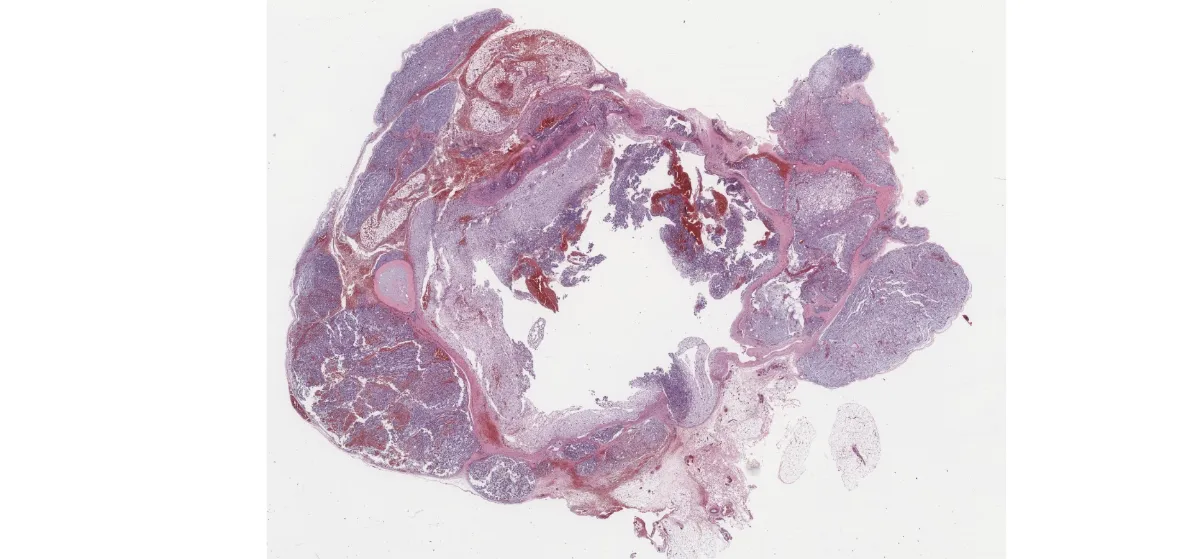

En la biopsia se observa una lesión multinodular, no encapsulada, con estroma mixoide y vasos en patrón plexiforme. Se identifican células pleomórficas, algunas multinucleadas, con citoplasma microvacuolado, dispuestas en patrón laxo. La inmunohistoquímica muestra positividad para S-100 (heterogénea), p16 (intensa), SOX9, andrógenos y SF-1, con un Ki67 del 25%. Mitosis ocasionalmente atípicas. Negatividad para múltiples marcadores epiteliales, musculares y neuroendocrinos.

HE – biopsia (3)

HE – biopsia (4)